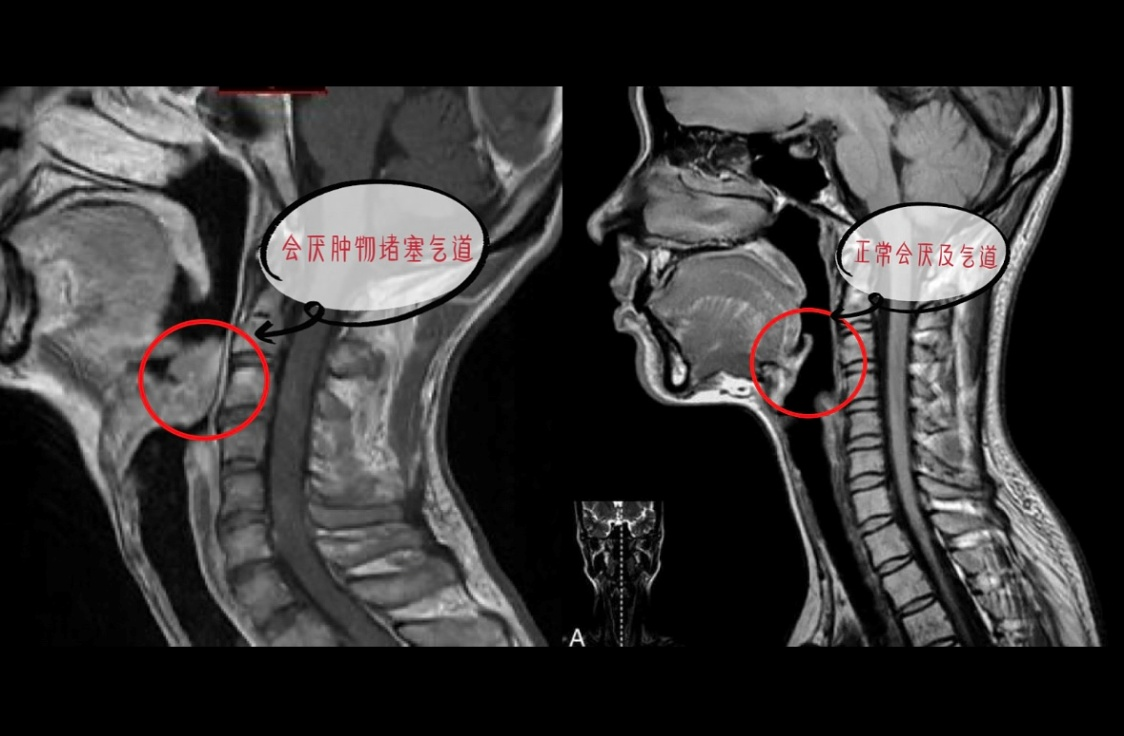

44岁的黄先生(化名)因咽喉疼痛、吞咽困难、咳血入院,确诊喉肿物后拟行声门上喉部分切除术。术前评估明确为“高危预期困难气道”:CT提示上会厌部占位伴积气、左侧颈部淋巴结压肿大,声音嘶哑与吞咽困难印证气道狭窄;同时合并双肺感染、支气管扩张、少量气胸、纵隔积气及肺大泡;耳鼻喉科医师首次喉镜检查可见会厌上菜花样新生物压迫会厌,“趴”在气道的开口牢牢堵住,其标志性解剖部位——声带,根本看不见,柔软的镜头反复旋转,也只能勉强从一个角度看到一点声带的结构,患者也是靠着这个通道艰难地呼吸通气。

▲ 左侧为患者颈部软组织MRI成像,右侧为正常颈部软组织成像 ▲ 左侧为患者颈部软组织MRI成像,右侧为正常颈部软组织成像